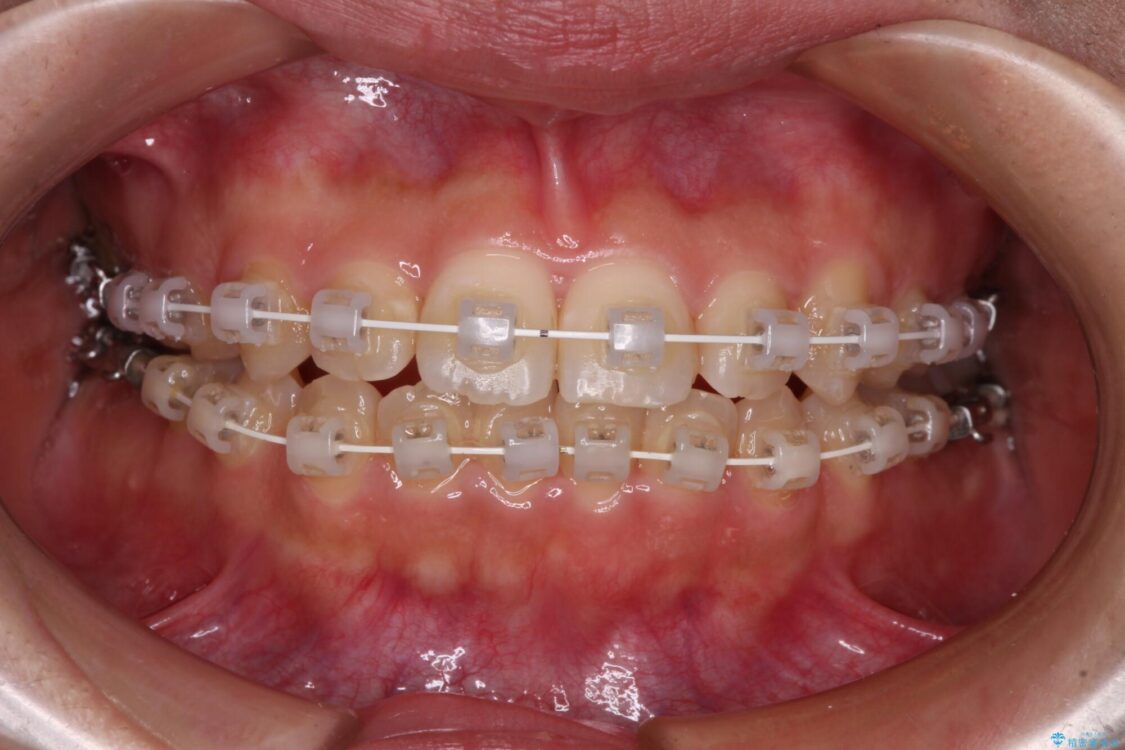

矯正装置

審美装置

マウスピース矯正のような自己管理の煩わしさは避け、早く治療を終えたいとのことで、ワイヤー装置による矯正治療を行うこととしました。

治療途中

• 【モニター】短期間で終わりたい ワイヤー装置での非抜歯矯正 治療途中画像